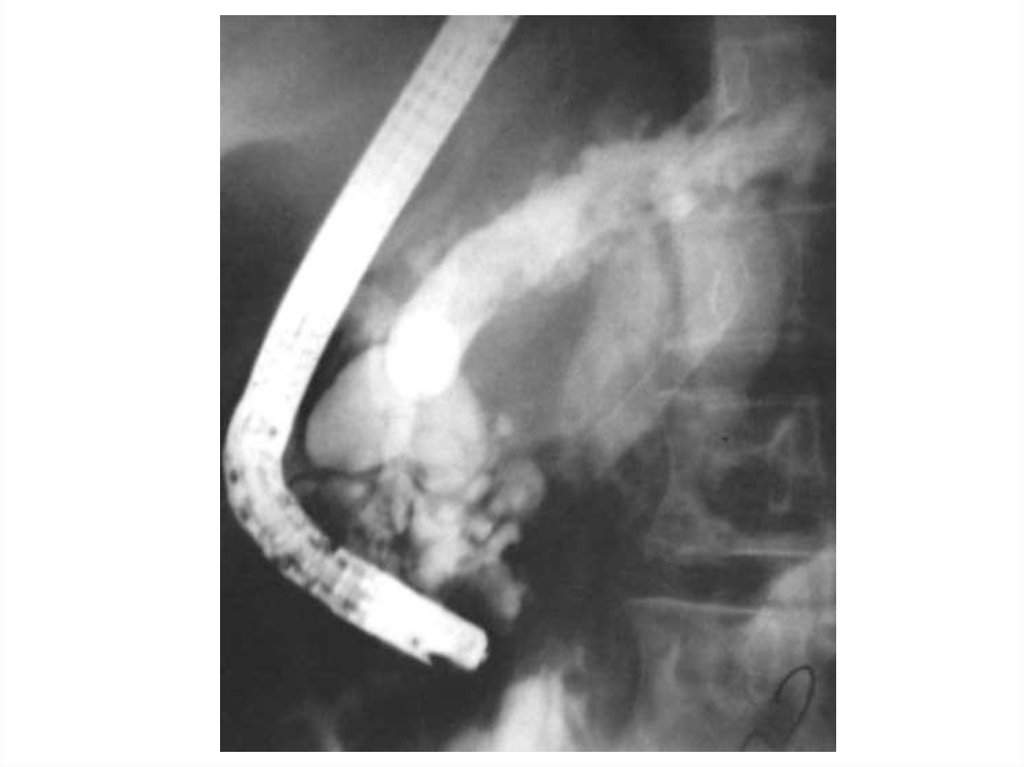

После эрхпг

После эрхпг 111 фотографий